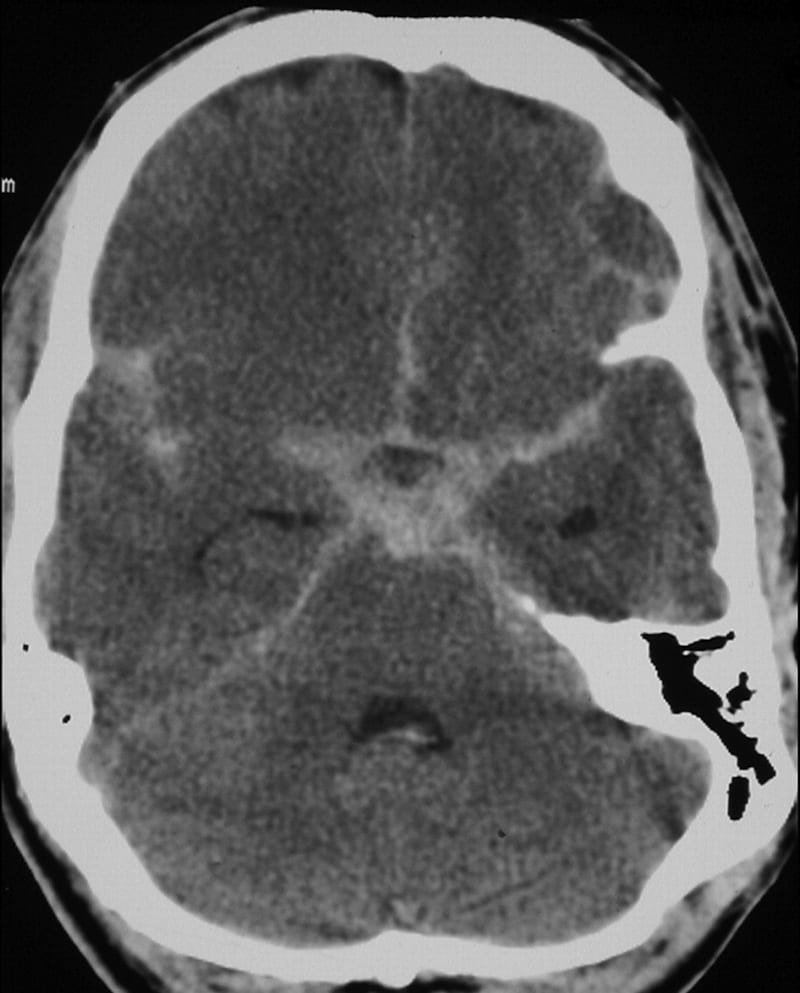

This ECG pattern is characteristic of raised intracranial pressure and is classically seen in the context of massive intracranial haemorrhage, particularly:

- Spontaneous subarachnoid haemorrhage

- Haemorrhagic stroke / intraparenchymal haemorrhage

Similar ECG patterns have also been reported in patients with raised ICP due to:

- Large-territory ischaemic stroke causing cerebral oedema (e.g. MCA occlusion)

- Traumatic brain injury

The main differential diagnosis for widespread “giant” T-wave inversion such as this is apical hypertrophic cardiomyopathy (HCM). Although myocardial ischaemia and electrolyte abnormalities can cause widespread T-wave inversion and QT prolongation, neither condition would cause the gigantic “cerebral T waves” seen here.

Obviously this is an artificial situation. This patient is likely to be deeply comatose on arrival to hospital — potentially with focal neurology — necessitating early airway intervention, measures to reduce ICP, and expedited neuroimaging to confirm the diagnosis. The ECG should not be relied upon to make this diagnosis!

In any case, their CT scan might look something like this…